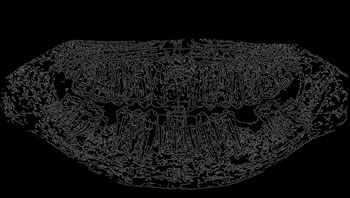

Image annotation

The process of annotating the images of our proposed data set occurred in two parts. First, it was initiated by the upper jaw through the annotation of the third right upper molar and making the annotation of all the teeth of the upper arch to the third left upper molar. Then, the same process was performed on the lower jaw with all the teeth, and in the same direction as the upper jaw, from left to right, starting with the annotation of the third right lower molar, and annotating all teeth from the lower arch to the lower third molar. Figure 4 illustrates the tooth annotation process through a panoramic X-ray image of the data set.

Figure 4: Annotation of the teeth.